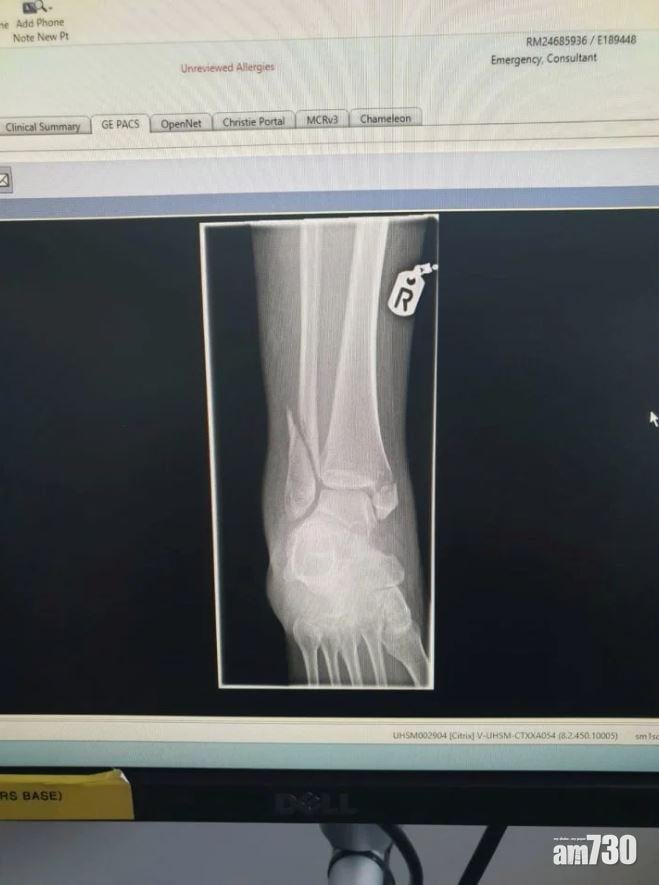

經X光診斷,小腿及腳掌等7處骨折。(互聯網)

英國托馬斯庫克航空(Thomas Cook Airlines)27歲空姐蓋瑞蒂(Eden Garrity),在去年8月一架由古巴飛往英國曼徹斯特的客機工作時,遇上冰雹風暴,強勁的氣流將她重摔在地,導致她小腿、腳踝及腳掌共7處骨折。當時蓋瑞蒂正推著餐車,機長開咪說有氣流,叫空姐空少坐下後僅5秒,客機便如坐過山車,向上急升500呎,蓋瑞蒂來不及反應,「氣流的力量將我釘在地板,腳踝完全折斷。」她要待客機降落曼徹斯特才送院治理,足足忍痛7小時。禍不單行的是,公司在一個月後倒閉,蓋瑞蒂康復之餘也要尋找新工作。